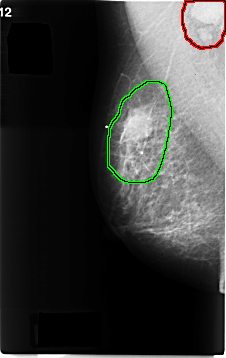

FILE: C_0195_1.RIGHT_MLO.OVERLAY

TOTAL_ABNORMALITIES 2

ABNORMALITY 1

LESION_TYPE MASS SHAPE ROUND MARGINS CIRCUMSCRIBED

ASSESSMENT 5

SUBTLETY 5

PATHOLOGY MALIGNANT

TOTAL_OUTLINES 1

BOUNDARY

ABNORMALITY 2

LESION_TYPE MASS SHAPE OVAL MARGINS ILL_DEFINED